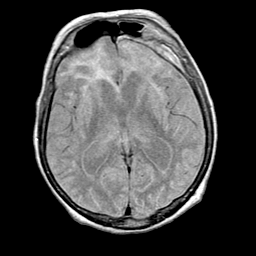

Pick's Disease, MR Study mr-pd -- Slice #11

[Home][Help][Clinical] Slice 11